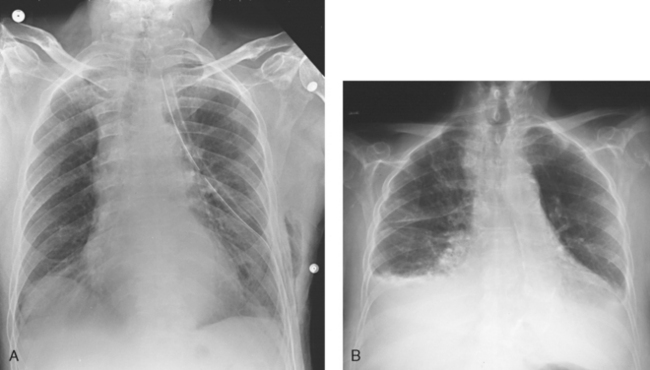

Fig. 28-13 Mobile AP chest radiographs performed in lateral decubitus positions in critically ill patients. A, Left lateral decubitus position. The patient has a large right pleural effusion (arrow) and no left effusion. Complete left side of thorax is visualized because of elevation on a block. B, Right lateral decubitus position. The patient has right pleural effusion (arrows), cardiomegaly, and mild pulmonary vascular congestion. Complete right side of thorax is visualized because of elevation on a block.